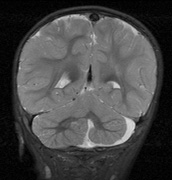

Fig. 6. Surveillance images of a 12-year-old girl with NF1 and an optic nerve glioma which has extended to involve the chiasm. Pre- (a) and postcontrast (b) T1-weighted coronal images reveal a large suprasellar mass with an enhancing component (arrow) seen separately from the normally enhancing pituitary gland. (c) Axial scans through the suprasellar cistern show the tumor is high signal on T2-weighted scans. (d) Enlargement of the chiasm, optic nerve and hypothalamus is visible on the post-contrast T1-weighted sagittal image. Although optic nerve glioma usually has a good prognosis (with visual function often remaining stable in the absence of any intervention66,67), chiasmal involvment is a poor prognostic indicator. A sign of chiasmal involvment may be new onset of endocrine disorders or nystagmus. Surgical excision of chiasmal gliomas carries a high risk of visual loss.68–70